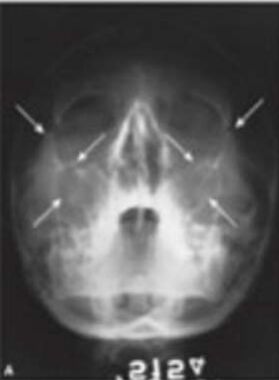

73.附圖所示之X光影像是由何種拍攝方式所產生? (A)posteroanterior projection(B)Waters projection(C)reverse Towne projection(D)oblique lateral projection

74.承上題,這種影像,最不適合評估下列何者? (A)慢性鼻竇炎(B)下顎骨髁頭骨折(C)眼眶骨骨折(D)顴骨骨折